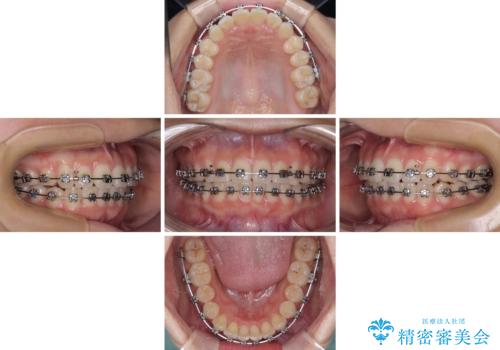

- メタルブラケット

- 1年6ヶ月

- 10-30回

治療中は大きなトラブルもなく、予定の1年半でスムーズに治療を終えることができました。